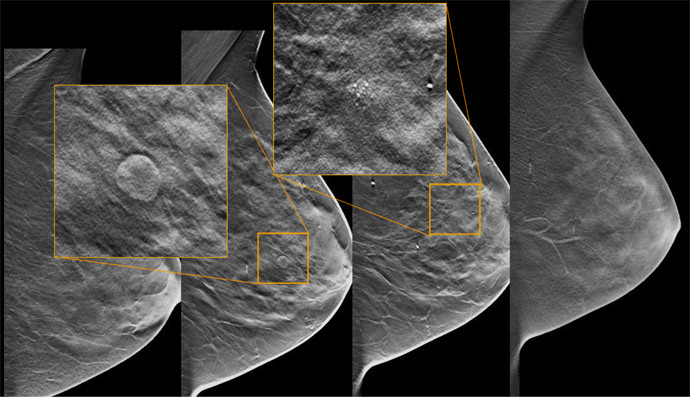

3Dマンモグラフィについて教えてください

通常のマンモグラフィに加え、乳腺を断層で撮影することができるものが3Dマンモグラフィとなります。1mm間隔で撮影をすることができるため、より詳しく検査をすることができます。

これにより、乳腺の重なった箇所の病変を見つけやすくなりました。

また、従来のものと比べ、圧迫による痛みは軽減されているのも大きなメリットとなっています。